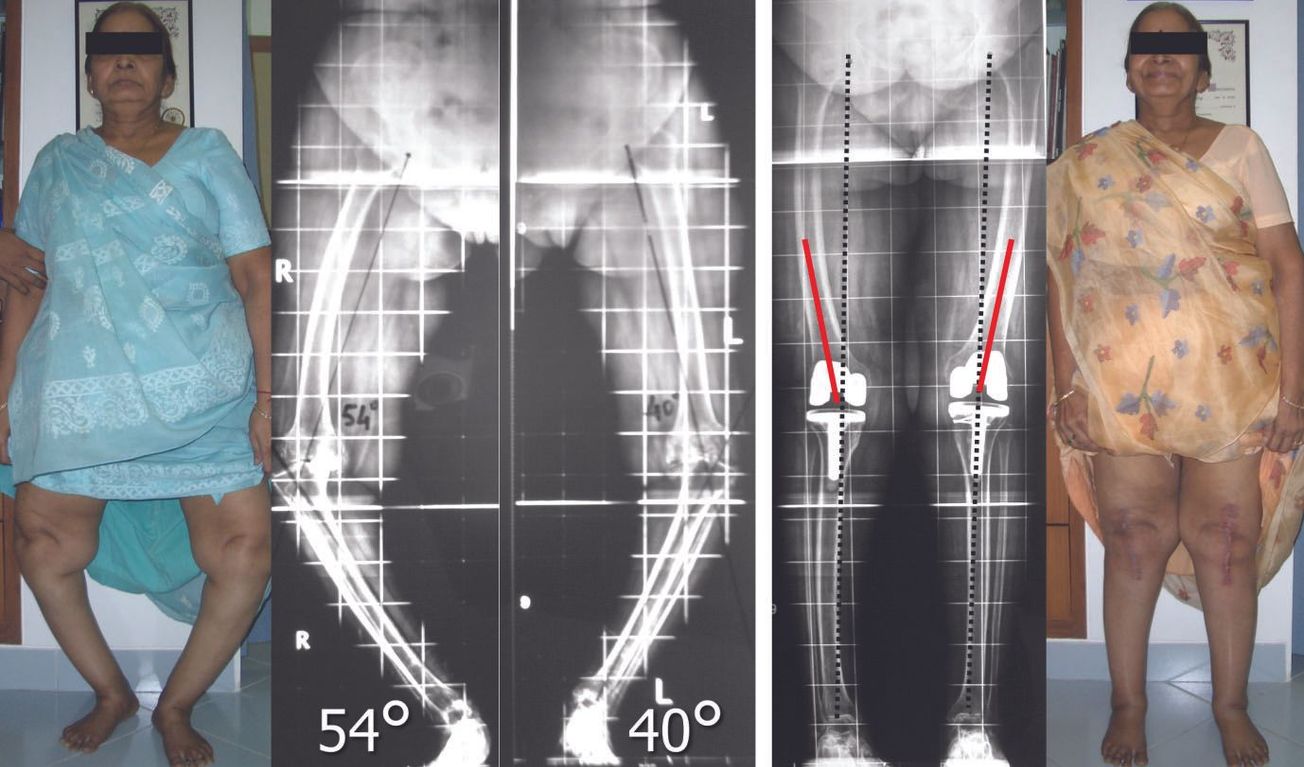

Technique PTG sur genu varum : Modalités illustrées des corrections à effectuer , Arun Mullaji Consultant Knee Surgeon Mullaji Knee Clinic, Mumbai, India 🖂 drarunmullajiclinic@gmail.com N°276 - Août/Septembre 2018 ● 8 min de lecture